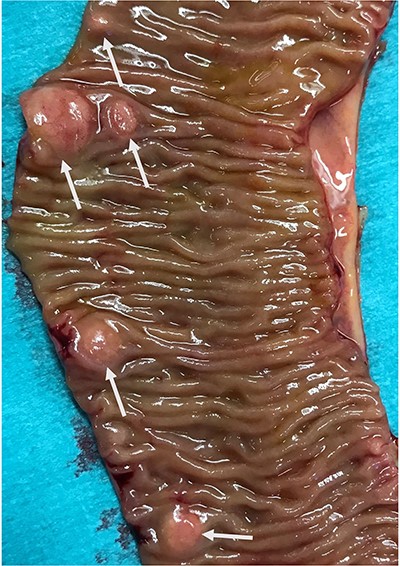

In view of suspected residual neuroendocrine disease not detectable on imaging, he underwent repeat laparotomy. Palpation of the entire small bowel from the Treitz ligament to the ileo-caecal junction was carried out and 70 cm of ileum harbouring multiple intramural deposits resected (Fig. 1). Following an end-to-end ileo-ileostomy, 280 cm of unaffected small intestine remained in situ. The postoperative course was uneventful. Histology demonstrated in total 25 well-differentiated NET (Fig. 2) positive for chromogranin (Fig. 3), synaptophysin and somatostatin receptor subtype (SSTR) 2A. Ki67 was <2% (G1). The tumours were staged as pT1m (largest 18 mm), pN1 (7/41) (largest lymph node 8 mm) and pL0 pV0. All resection margins were tumour-free. At the last follow-up 9 months after completion surgery the patient was alive with no evidence of disease on imaging or biochemistry.

Typical histologic appearance of a well-differentiated neuroendocrine tumour of small bowel (right side, arrows), compared with unaffected ileum (left half of image) on haematoxylin & eosin staining (original magnification ×10).